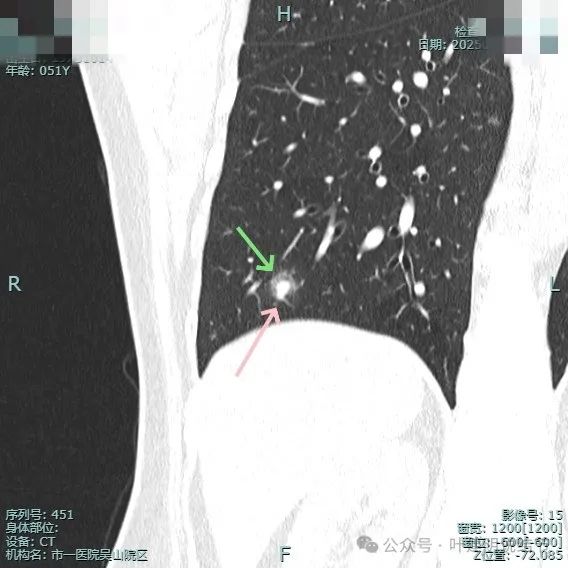

再看在我门诊时2025年1月14号复查的靶扫描影像:

非薄层上见病灶混合密度,整体轮廓较清。

实性成分明显,但缺乏收缩力;边上是磨玻璃成分,整体轮廓较清;邻近血管走行,但没有形成血管弯征。

混合密度,整体轮廓较清,瘤肺边界欠清,整体看没有收缩力。

边缘细毛刺,不太锐利;外围磨玻璃成分,瘤肺界限欠清;中间实性成分明显但缺乏收缩力,实性部分没有明显毛刺征。